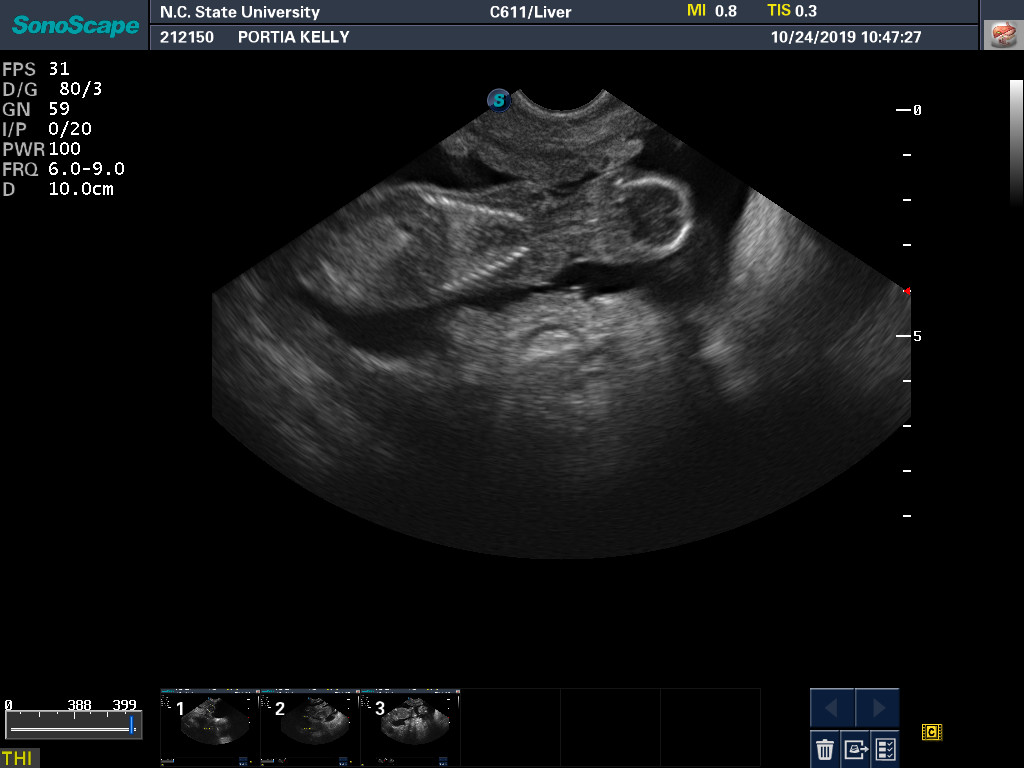

24 Oct

Portia's ultrasound today again showed healthy puppies. Blood was drawn to check Portia's progesterone levels. During a pregnancy, the progesterone level slowly drops. If the progesterone level gets too low too quickly, it can result in preemie puppies.

Here are two ultrasound pictures: